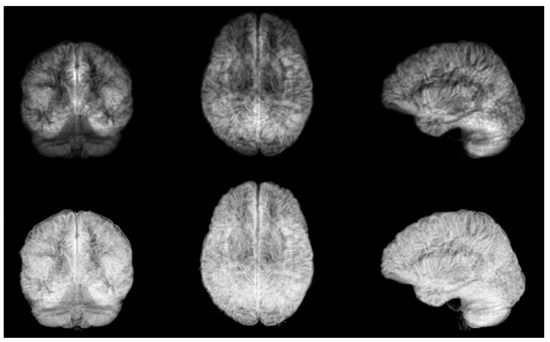

Figure 2.

Top: mean grey matter likelihood projections on coronal, axial and sagittal planes, for one subject. Bottom: standard deviation grey matter likelihood projections on coronal, axial and sagittal planes, for the same subject.